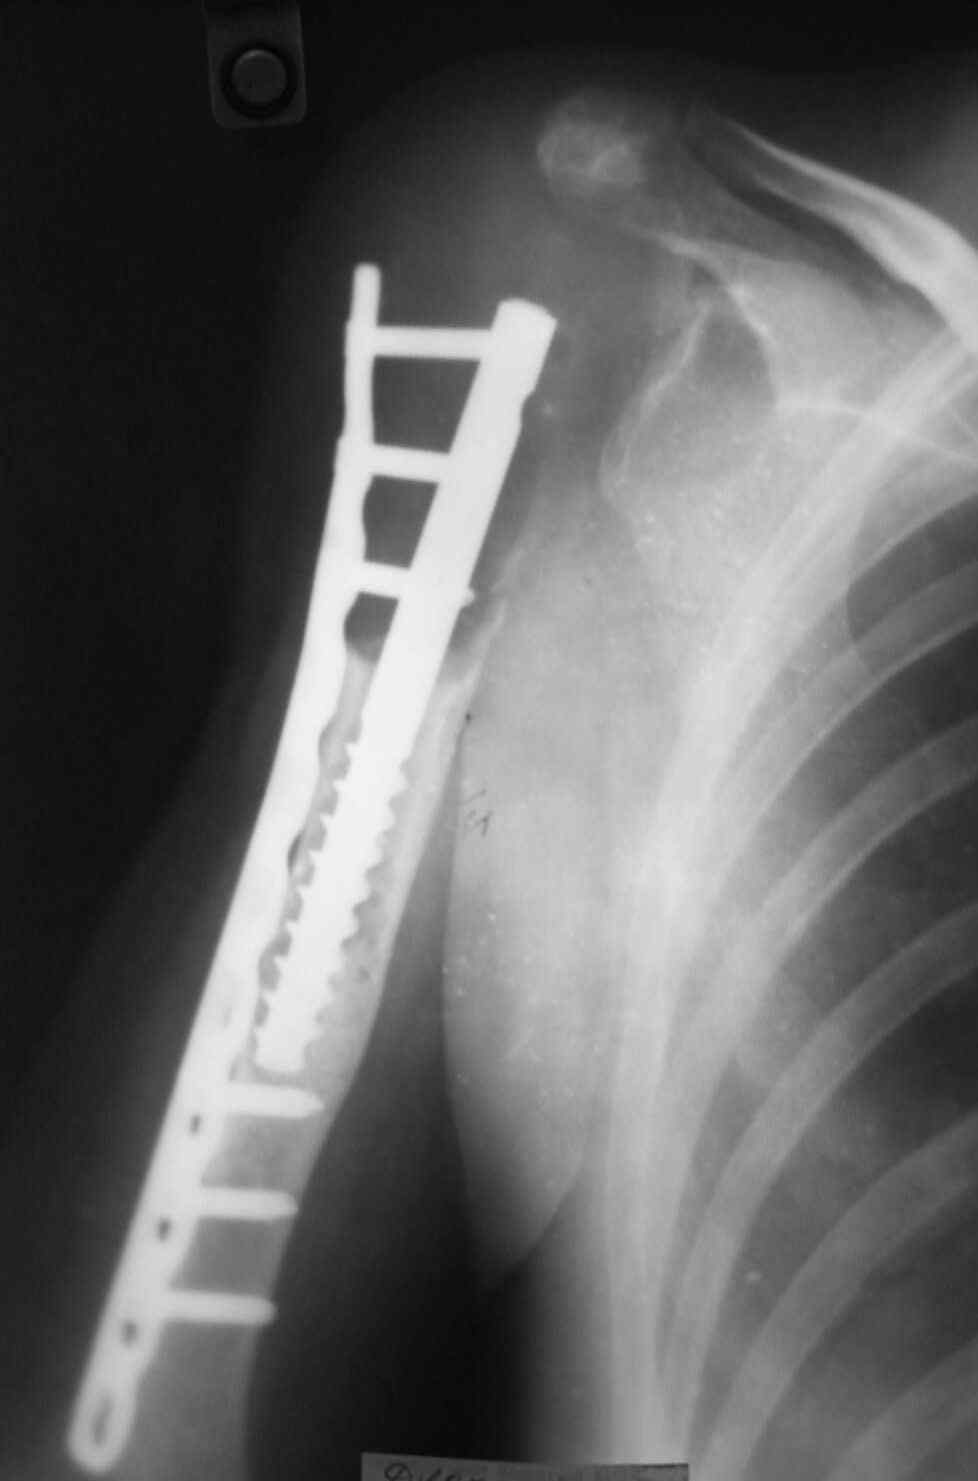

Больная 34 года операрована 14 лет назад по поводу литической формы ОБК головки плечвой кости

14 лет назад больной имлапнтирован протез плечевой кости выполненый по методике Воронцова на штифте-штопоре Сиваша,за 2 года до имлапнатации в онкологическом учереждении больной выполнена резекция проксимальоной части плечевой кости по поводу ОБК, ксенотрансплантации головки, и последующем его удалением на фоне гнойного процесса. У больной имелся втянутый обширный рубец и болтающееся плечо, афункциональная верхняя конечность, выраженный косметический дефект.П/опрационный период без осложнений, сохранялась выраженная контрактура в плечевом суставе, но стаилизация плеча и косметический эффект больную устраивал,даллее контакт с больной был утерян ( поменяла место жителсьтва. Через 14 лет полноценной жизни сельской жешщины ,больная нашла нас с клиникой выраженной нестабильности протеза. Категорически отказалась от замены протеза.

Выполнена операция- малоинвазивно проведена LCP пластина в образованный канал над головкой протеза, фиксирована к протезу и дистально к плечевой кости, на зоной резорбции трепонирована кость, удалена соединительно-тканная оболочка, полость заполнена chronOS. П/о период без осложнений, клиника нестабильность купирована.Прошло 2 года по телефону сообщила, что у нее все хорошо, продолжает жить счастливой жизнью сельской труженицы

Головка отлита из акрилоксида( то чем мы располагали в прошлом веке), он полность Р-прозрачен, по методике Воронцова рекомендовалось добавлять Р-контрастные добавки,например сульфат бария, учитывая, что он давал раковины в полимере, мы это не сделали.Кстати, довольно крепкий получился, затупили 2 сверла.

Функциональный результат нам известен в полеоперационном периоде

отведение 10 гр, сгибание 60 гр, разгибание 0, ротация 5гр, что соответсвовало функции до наступления нестабильности.

К сожаления, вся информация о нынешем состоянии больной получена по телефону - болей нет, объм движения не уменьшился, полная нагрузка на конечность, из наших рекомендаций по ограничениям соблюдает только одно- не выкручивает белье.